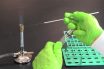

Aseptic

Free from infection or septic material; sterile, free from pathogenic microorganisms. Free of disease or spoilage causing organisms. Free from contamination by hannful bacteria, viruses or other micro-organisms. Sterilised, or involving sterilisation, and therefore without infection. Sterile; absence of pathogens. Devoid of microorganisms that can cause illness.

Asepsis

Free from infection. The prevention of contact with microorganisms. The absence of viable organisms. The complete absence of bacteria, fungi, viruses, or other microorganisms that could cause disease. Asepsis is the ideal state for the performance of surgical operations and is achieved by using sterilization techniques. A technique to produce a germ-free environment to protect…